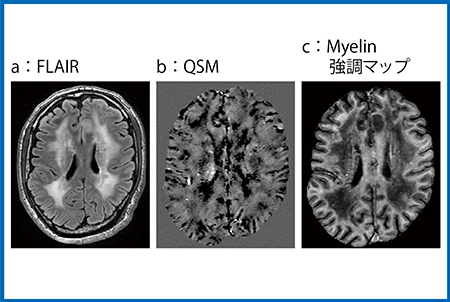

症例2は,FLAIRで白質の高信号がびまん性に認められ(図4 a),正常な白質はやや黒く描出されるQSMでは不均一な信号上昇を示した(b)。また,QPMから作成したミエリンマップでも白質は低信号を呈しており,髄鞘密度の減少が示唆された(図4 c)。

図4 症例2:COL4A1遺伝子変異疾患